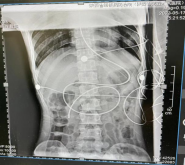

图为白蓉护士长盲插为两名重症患者置鼻空肠营养管